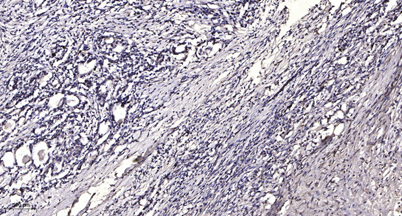

IHC

IHC-p 1:50-300